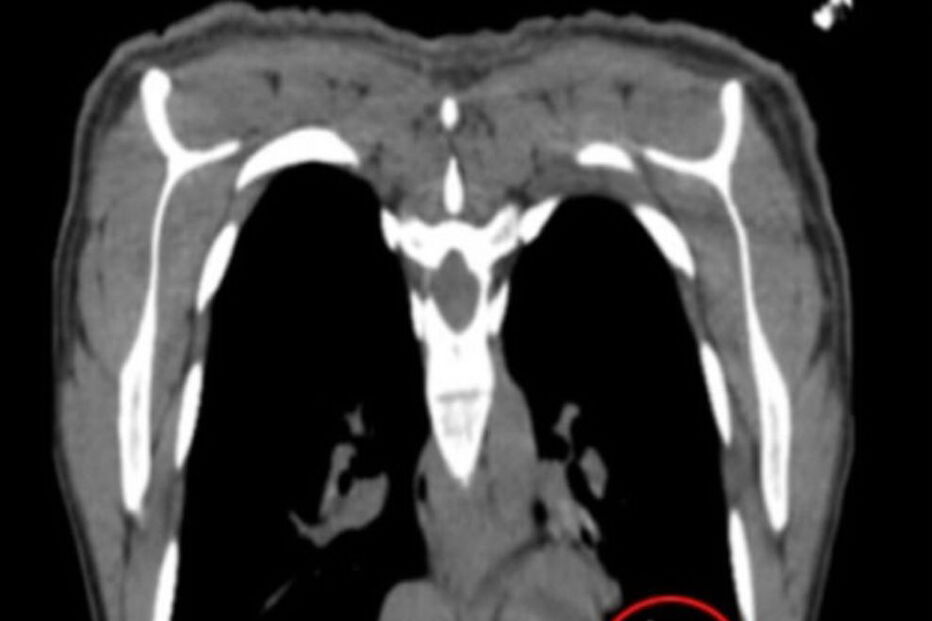

Exames posteriores mostraram que o implante estava instalado no fundo do pulmão esquerdo. No relatório médico, os profissionais sugeriram que o dispositivo tenha migrado para o pulmão através de um vaso sanguíneo, ao ter sido colocado muito profundamente. Outra das hipóteses colocadas foi a prática de exercicío fisíco intenso logo após a colocação, o que pode aumentar o risco de migração vascular.